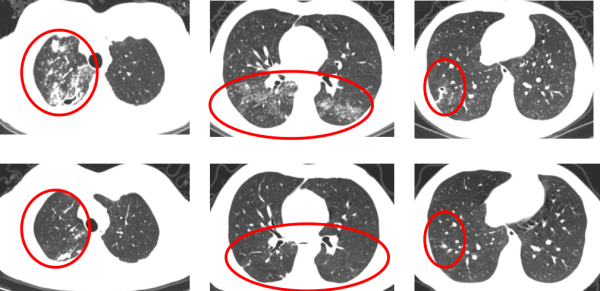

在治疗过程中,耐药中医肺病科医疗团队密切关注李勇的病情变化和身体反应,经过6个月的规范治疗,李勇的病情得到了明显的改善,复查结果显示,他肺内病灶明显吸收,空洞已闭合,痰菌转阴,无咳嗽,身体状况逐渐恢复,顺利停药观察。

治疗6月前后胸部CT比较(上排为治疗前,下排为治疗后)可见肺内病灶明显吸收,空洞已闭合